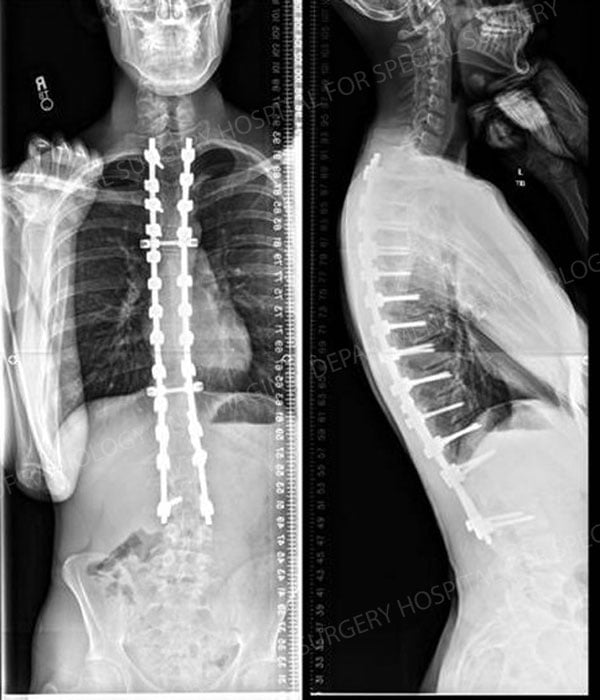

Figures 1 & 2:

16-year-old male who presented with Scheuermann kyphosis

Figure 2. Post operative x-ray images demonstrating the surgical correction that was achieved.